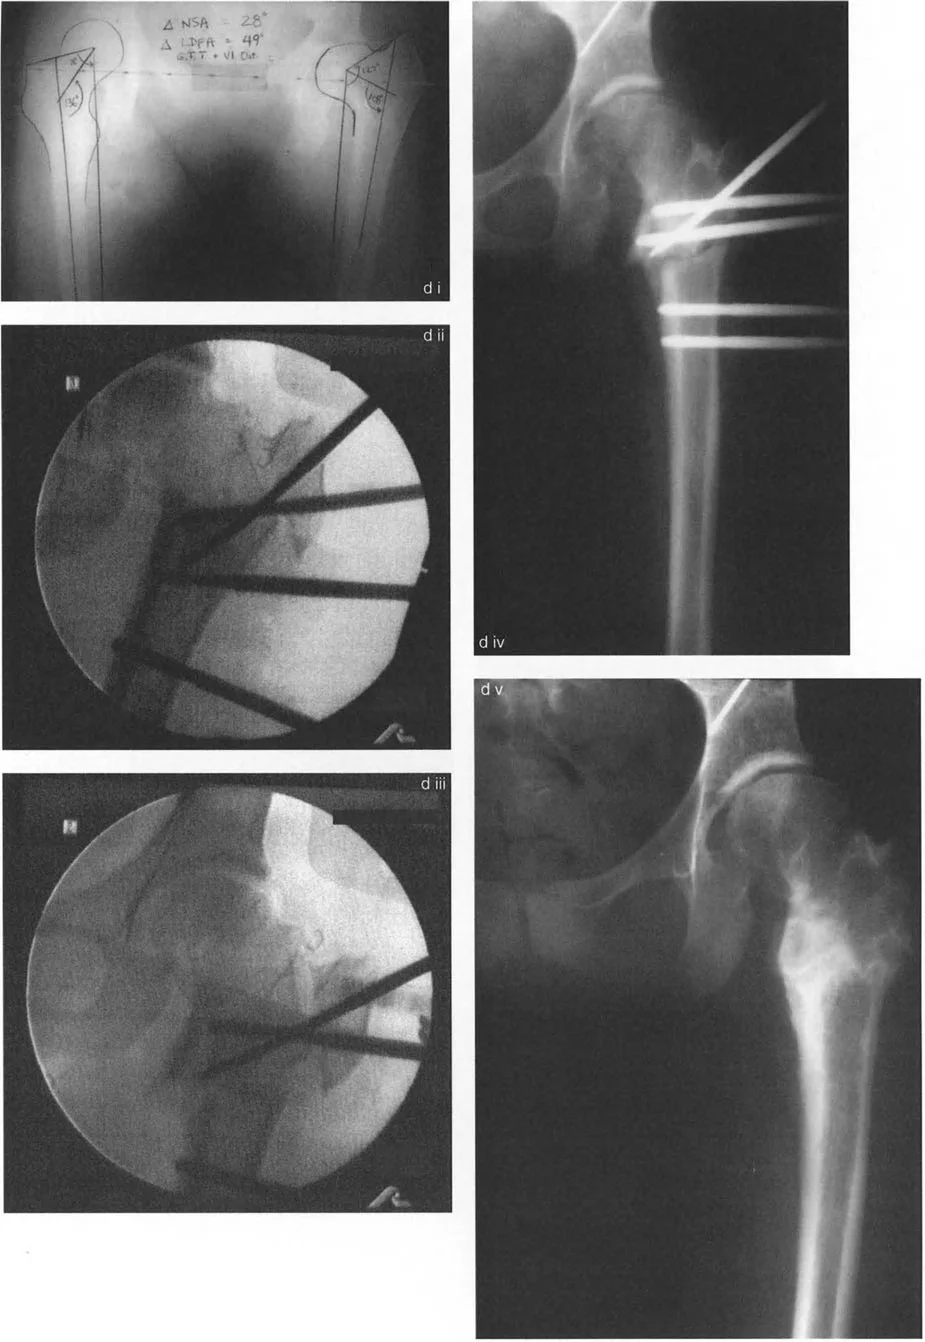

- طريقة واغنر (Wagner Osteotomy): وصفها واغنر عام 1978. تتضمن قطع عظم الفخذ تحت المدور (Subtrochanteric) مع نقل للمدور الكبير. هذا الإجراء يصحح كلاً من الزاوية بين عنق وجسم الفخذ (NSA) والزاوية الميكانيكية لعظم الفخذ القريب (MPFA) إلى الوضع الطبيعي. يتم تثبيت العظم بعد التصحيح عادةً بمثبت خارجي أو صفائح ومسامير.

صور توضح حالة كسع الورك مع تضخم المدور الكبير قبل وبعد إجراء قطع عظم واغنر، حيث يتم تصحيح المحاذاة ونقل المدور الكبير.

* **طريقة مورشر (Morscher Osteotomy):** بديل لطريقة واغنر. تستعيد هذه الطريقة الزاوية بين عنق وجسم الفخذ عن طريق إجراء قطع عظم تحت المدور بالزاوية المطلوبة. يتم إطالة جسم الفخذ وتحريكه جانبيًا على طول ميل هذا القطع. يتم نقل المدور الكبير إلى الأسفل والجانب عن طريق إزالة أسطوانة عظمية من قاعدته ثم وضعها بين المدور وجسم الفخذ لملء الفراغ الجانبي. تصحح هذه الجراحة كلاً من الزاوية بين عنق وجسم الفخذ والزاوية الميكانيكية لعظم الفخذ القريب إلى الوضع الطبيعي. ومع ذلك، لا تغير هذه الطريقة اتجاه رأس الفخذ في التجويف الحقي، وإذا كان هذا التغيير مطلوبًا، تُفضل طريقة واغنر.

صور توضح حالة كسع الورك مع تضخم المدور الكبير بسبب مرض بيرثيز، وعلاجها باستخدام قطع عظم مورشر مع التثبيت الداخلي.

تسلسل صور بالأشعة السينية يوثق تقنية نقل المدور الكبير بالمنظار، من إدخال سلك التوجيه والقطع إلى التثبيت بالمسامير.